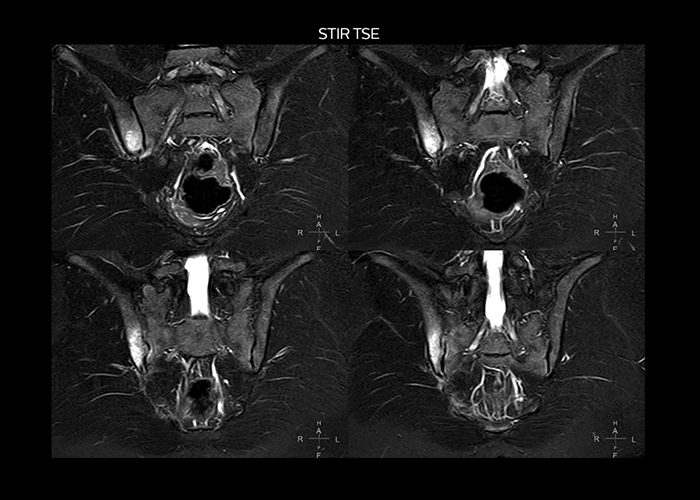

“On average, we scan about 80 patients per day, but on some days we scan well over 100 patients. The scanner is in use 7 days per week, operated 20 hours per day on week days and 8 hours per day in the weekend,” Mr. Tuna says. “To avoid coil changes we plan examinations of similar anatomies back to back, such as head and spine. Multiva helps us here a lot because coils don’t need to be changed frequently. Moreover, thanks to parallel imaging technology and 16-channel HeadSpineTorso and 8-channel MSK coils we are able to achieve excellent image quality. In this way Multiva helped us to increase both image quality and productivity.” “Neurological cases, such as brain and spine imaging, represent the largest share in our MR scanning, followed by musculoskeletal cases. In general, we use simple and basic imaging protocols. But occasionally, we use advanced techniques for problematic cases if necessary.